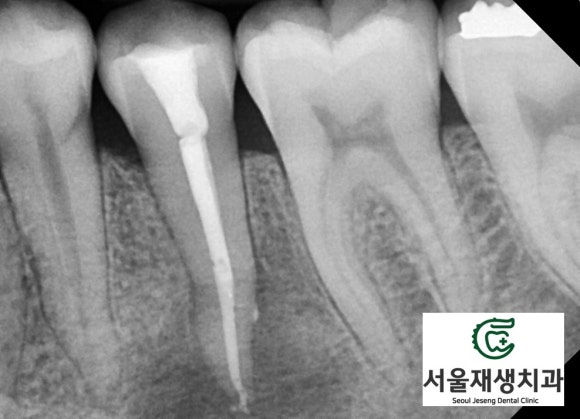

X-ray를 통해 뿌리 끝 염증을 관찰!

![[치외치신경치료] 뿌리 끝 염증이 커서 발치해야된대요! 치아 머리에 볼~록! 알고보면 무서운 작은 혹 (서울재생치과) 관련 이미지 10](https://pub-9f2bb3498faf4d1d8714b41df24753e3.r2.dev/content/clinics/archive/nqmm0udu86/naver_blog/honeybeevuvu/assets/by_hash/10f59e16229876a515c5aab5294ce63cd502d1050a2410575aae82bc50a5cedc.jpg)

치과 엑스레이 검사의 가장 기본이 되는

파노라마 엑스레이입니다.

조금만 더 확대해볼까요?

![[치외치신경치료] 뿌리 끝 염증이 커서 발치해야된대요! 치아 머리에 볼~록! 알고보면 무서운 작은 혹 (서울재생치과) 관련 이미지 11](https://pub-9f2bb3498faf4d1d8714b41df24753e3.r2.dev/content/clinics/archive/nqmm0udu86/naver_blog/honeybeevuvu/assets/by_hash/7f5faaa71c7684e360752df8620c74f0f6416559dc3e7d4c32e5f10f79f44df5.jpg)

아하...

아래 어금니 앞에 있는

작은 어금니의 뿌리 주위로

심상치 않은 기운이 느껴집니다.

![[치외치신경치료] 뿌리 끝 염증이 커서 발치해야된대요! 치아 머리에 볼~록! 알고보면 무서운 작은 혹 (서울재생치과) 관련 이미지 12](https://pub-9f2bb3498faf4d1d8714b41df24753e3.r2.dev/content/clinics/archive/nqmm0udu86/naver_blog/honeybeevuvu/assets/by_hash/d9165ef2b2fa57c1c71cddfbb8a791e8a8dfa368a13539ce3b5028aab989a652.jpg)

뼈를 광범위하게 녹이고 있는

뿌리 끝 염증!!

치아 신경은 이미 감염되었고,

감염 부산물들이 뿌리 끝에 나있는

작은 구멍을 통해 배출되다보니

뼈까지 손상을 시키게 된 것이죠...